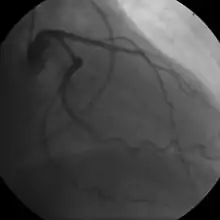

Coronary angiogram of a man

Coronary angiogram of a woman

For symptomatic people, stress echocardiography can be used to make a diagnosis for obstructive coronary artery disease.[68] The use of echocardiography, stress cardiac imaging, and/or advanced non-invasive imaging is not recommended on individuals who are exhibiting no symptoms and are otherwise at low risk for developing coronary disease.[68][69]

The diagnosis of microvascular angina (previously known as cardiac syndrome X – the rare coronary artery disease that is more common in women, as mentioned, is a diagnosis of exclusion. Therefore, usually, the same tests are used as in any person with the suspected of having coronary artery disease:[70]

Stable angina is the most common form of ischemic heart disease, and is associated with reduced quality of life and increased mortality. It is caused by epicardial coronary stenosis which results in reduced blood flow and oxygen supply to the myocardium.[72] Stable angina is characterized as short-term chest pain during physical exertion caused by an imbalance between myocardial oxygen supply and metabolic oxygen demand. Various forms of cardiac stress tests may be used to induce both symptoms and detect changes by way of electrocardiography (using an ECG), echocardiography (using ultrasound of the heart) or scintigraphy (using uptake of radionuclide by the heart muscle). If part of the heart seems to receive an insufficient blood supply, coronary angiography may be used to identify stenosis of the coronary arteries and suitability for angioplasty or bypass surgery.[73]